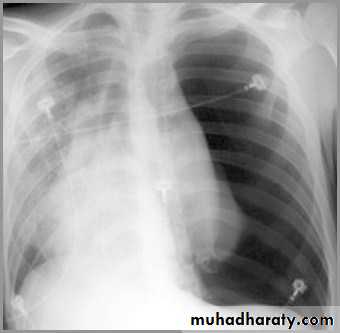

Tension pneumothorax

Progressive loss of air into pleural space causing a shift of the heart and mediastinal structures away from side of pneumothoraxOpposite lung is compressed

Respiratory function severely compromised